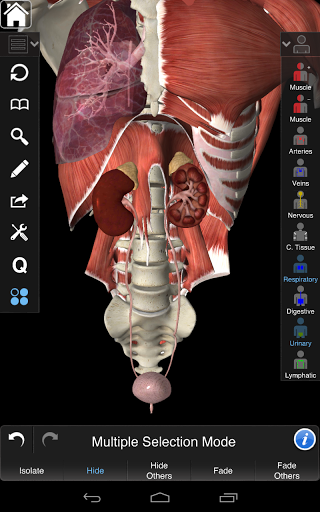

Essential Anatomy 3 represents the latest in groundbreaking 3D technology and innovative design. A cutting edge 3D graphics engine, custom built by 3D4Medical from the ground up, powers a highly-detailed anatomical model and delivers outstanding quality graphics that no other competitor can achieve.

Essential Anatomy 3 is responsive, visually stunning and effortless. The app is fully 3D, meaning that you can view any anatomic structure in isolation, as well as from any angle.

Clever functionality found within the app allows the user to strip away layers of muscle via the ‘scalpel’ tool. This app provides users with the ability to turn on/off systems without the need to deselect individual structures or muddle through a multitude of predefined regional tabs, like other apps.

---- Multiple Selection Mode - Hide/Fade/Isolate individual or multiple structures